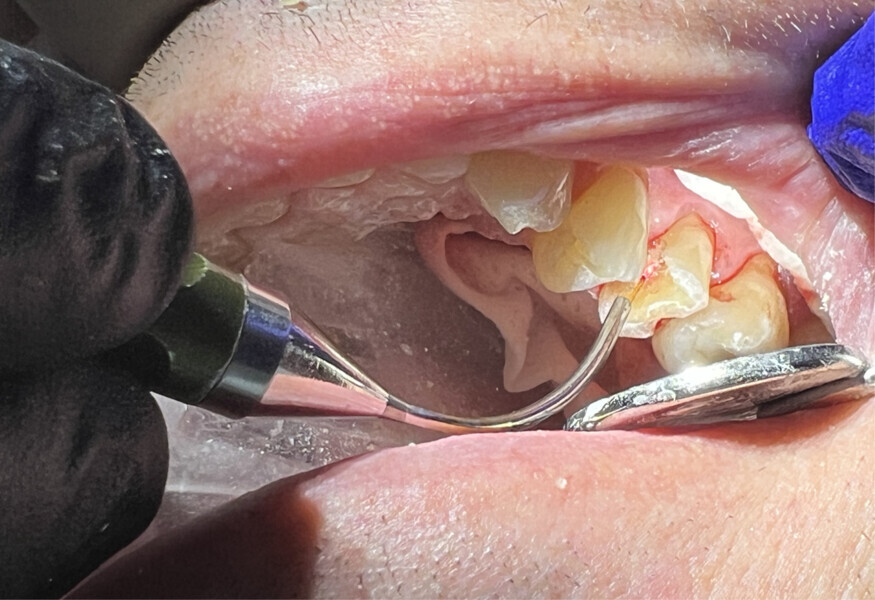

Local anaesthetic was infiltrated into the buccal vestibule. The caries and affected tooth structure were removed with carbide and diamond burs. A pulpal exposure was not observed, but thin tooth structure was noted covering the pulp (Fig. 11). The Nd:YAG laser was set on the ablation setting and applied to the area over the thin dentine overlying the pulp at 50–75 J. The laser was then used on the same setting up to 162 J to sterilise the surrounding tooth structure and for biostimulation as described in the prior case. A small amount of GC FujiCEM was placed to cover the underlying pulp. A core build-up was then applied utilising RelyX Unicem resin on the surrounding sound tooth structure to ensure a good bond between the core material and dentine. Crown preparation of the tooth was completed. An impression was taken, and a provisional crown was fabricated and cemented with IRM. The patient returned for definitive crown insertion two weeks later and reported a lack of sensitivity during the period since her prior appointment. The provisional crown was removed, the definitive crown was luted with RelyX Unicem, and the occlusion checked and adjusted as needed.

Fig. 11: Pulpal tissue seen below a thin layer of dentine after caries removal.